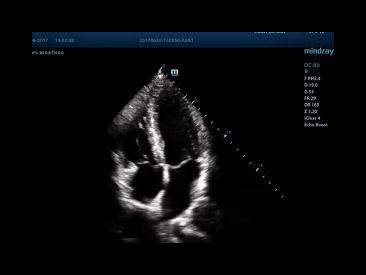

Auto EF

One intelligent way to analyze 2D echo clips to automatically recognize diastole/systole frames and output EDV/ESV/EF etc. results by Simpson method.